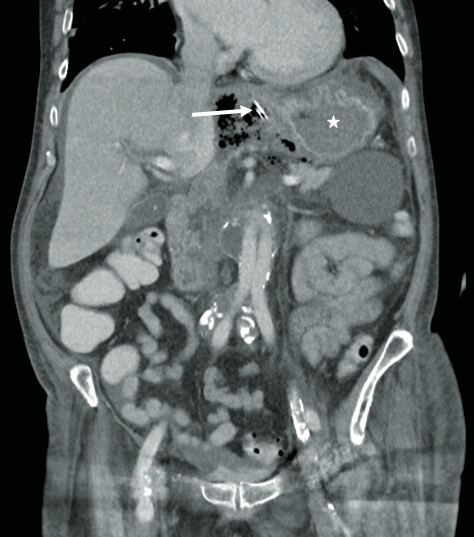

Diagnostik: Eine CT ergab eine extragastral liegende Magensondenspitze und ein Luft-Flüssigkeit-Gemisch intraabdominell im Oberbauch (Abb. 1).